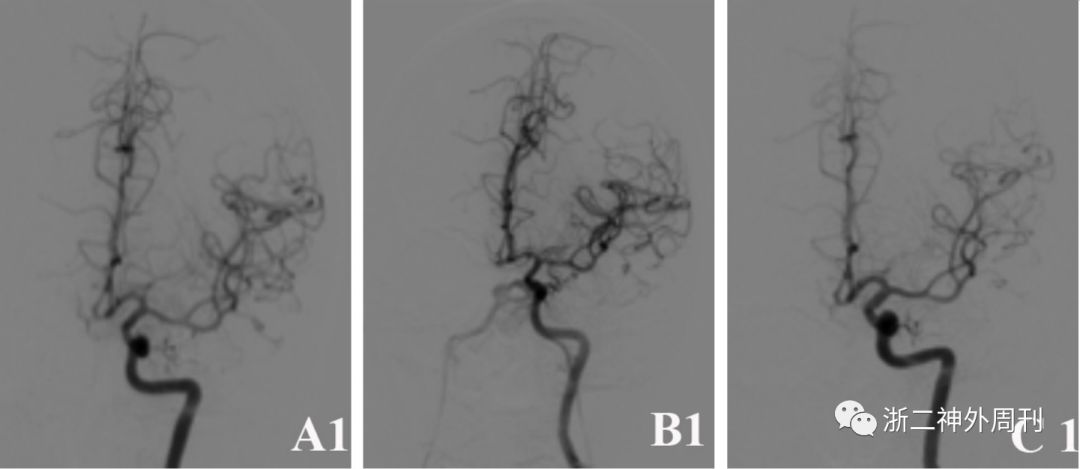

入院后急诊DSA检查,证实左侧颈内动脉脉络膜前动脉段动脉瘤,约2.2mm×3mm,颈宽2.2mm(图1A1-A3)。

图1. A1-A3 术前DSA检查提示左侧颈内动脉脉络膜前动脉段动脉瘤;B1-B3:术后4天复查DSA提示动脉瘤夹闭满意,无残留;同时发现左侧海绵窦硬脑膜动静脉瘘,左侧脑膜垂体干动脉供血,瘘口位于左侧海绵窦后部,双侧岩下窦引流,静脉窦血流方向正常,无皮层静脉引流。C1-C3: 随访观察8月后复查DSA提示动脉瘤无复发,硬脑膜动静脉瘘消失。